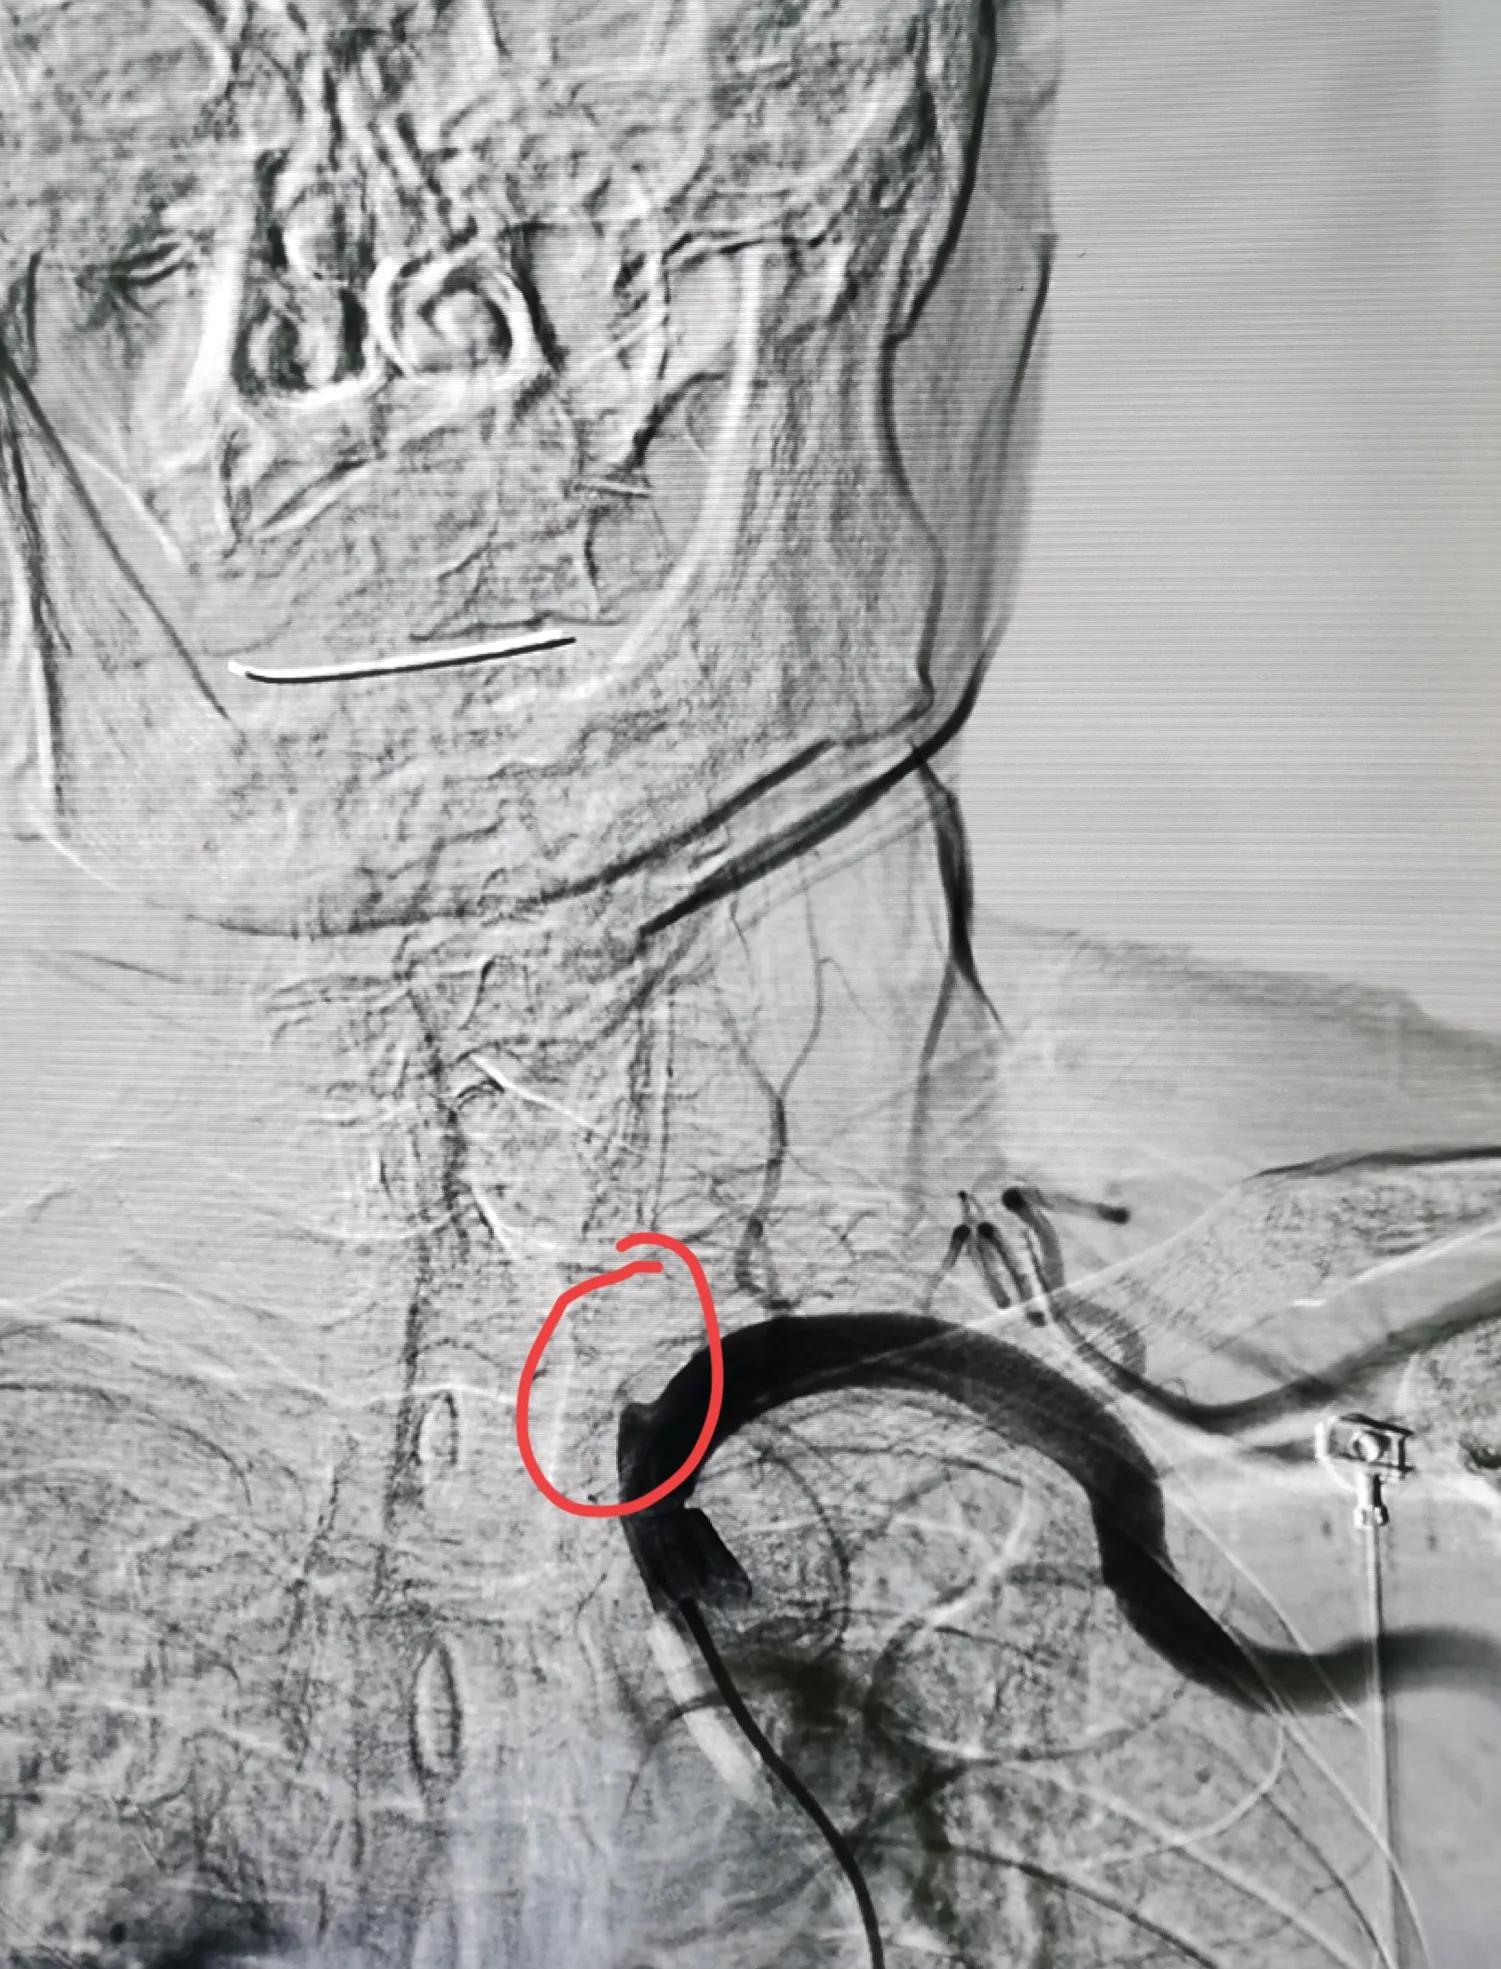

于是,次日,做了局麻下脑血管造影,可见:左侧椎动脉全程闭塞,仅仅在起始处见到一个残端,右侧椎动脉中度狭窄,

左侧椎动脉闭塞

右侧椎动脉中度狭窄